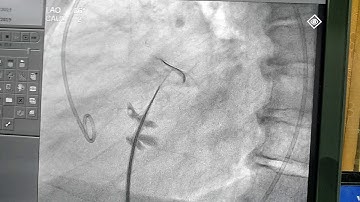

How to echocardiographically guide a trans-septal puncture - PITLOC Protocol